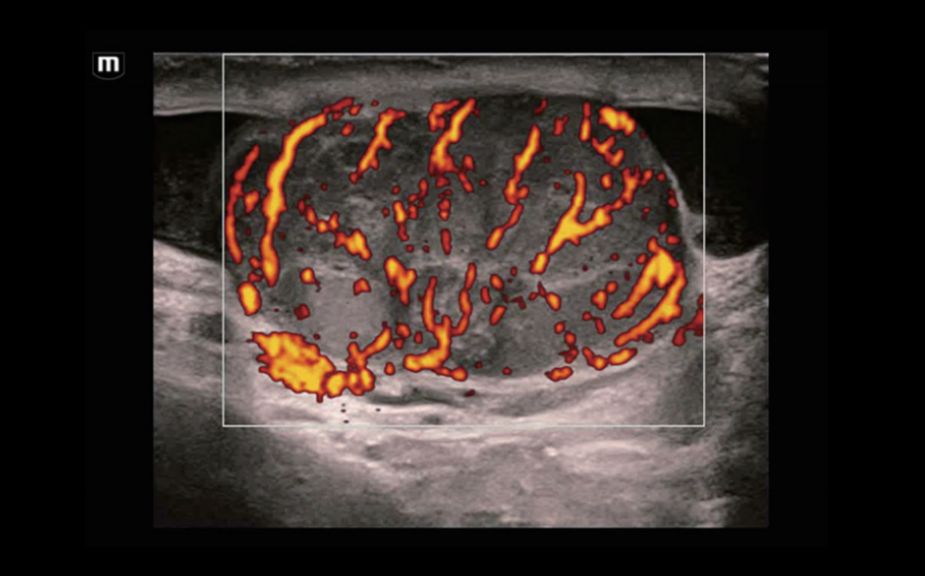

A Novel Approach of Vascular Hemodynamics: V Flow

The color coded vector arrows indicate the velocity magnitude and direction of blood cells. With an ultra-high frame rate, V Flow provides extremely vivid, accurate and angle-independent visualization of complex vascular hemodynamic profiles with comprehensive data information.

V Flow

A Novel Approach of Vascular Hemodynamics: V Flow

The color coded vector arrows indicate the velocity magnitude and direction of blood cells. With an ultra-high frame rate, V Flow provides extremely vivid, accurate and angle-independent visualization of complex vascular hemodynamic profiles with comprehensive data information.

V Flow